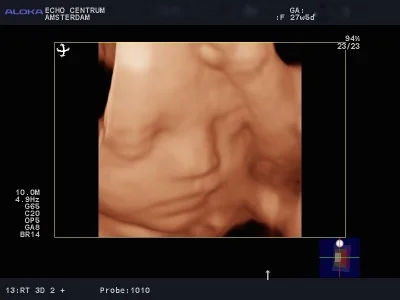

Onlangs had ik een hele leuke ervaring. Ik ben een gepensioneerd gynaecoloog, en was vroeger zeer begaan met mijn verloskundige patiënten. Mijn schoondochter en zoon nodigden mij uit om mee te gaan naar een "pretecho"van dr. Papa in Amsterdam. Wij, gynaecologen, hebben geweldige vooroordelen tegen een zogenaamde pret echo en vinden ze vaak overbodig. Nou dit pakte anders uit. We werden verwelkomd door een bijzonder charmante, leuke en vlot bespraakte Nederlandse Antiliaan: Elvin Papa, arts echoscopist. Daar zat hij in zijn spreekkamer, in een prachtig pand, achter een prachtig echo apparaat, dat voor mijn toenmalige ziekenhuis te duur was om voor ons gynaecologen aan te schaffen!! Alles werd getoond, het hele lichaampje van de baby. Alle organen, het geslacht, hart en bloedvaten noem maar op. Prettig was dat je in 3D een hele goede indruk krijgt van het gezichtje. Het hele onderzoek verliep voorspoedig en was heel relaxed. Papa doet veel aan nascholing en houdt de ontwikkelingen op echo gebied heel goed bij. Echo onderzoek kan heel vervelende zaken aan het licht brengen. Wij hadden een goed nieuws echo, dus dat is feest en lol. Belangrijk lijkt mij wel dat je met een slechte echo bij Elvin Papa in goede handen bent. Hij zal weten hoe je te troosten en hoe je door te verwijzen. Hopelijk hoeft dat niet vaak. Ik wens hem nog veel succes toe.

Bij deze willen wij je nog even bedanken voor de mooie en bijzondere echo die je van onze tweeling hebt gemaakt (de echo lukte zo goed!). Aangezien we ons nogal veel zorgen maakten was de echo precies de positieve input die we nodig hadden. We zijn natuurlijk een beetje beroepsgedeformeerd en wij vonden het schitterend dat je met de moderne technieken (je superecho-apparaat!!) de anatomie van die piepkleine mensjes zo goed kunt zien! Nogmaals ontzettend bedankt.

Al jaren hoorde ik vele goede verhalen van cliënten en collega's. Toen ik zelf zwanger was, wilde ik dan ook graag eens een echo bij drs. Papa mee maken. En ik begreep meteen waarom iedereen altijd zo enthousiast was! Via de (2,3 & 4D) echo van Elvin Papa maakten wij voor het eerst kennis met ons kindje. Dit was toch weer heel anders dan de standaard medische echo's die hieraan vooraf waren gegaan. Ik was ontroerd! Sinds deze echo voelde ik meer 'band' met ons ongeboren kindje. Wij zagen op de echo dat hij voortdurend zijn handjes voor zijn gezicht hield en Elvin voorspelde dat wij dit vast terug zouden zien als hij eenmaal in de wieg lag. En ja hoor, nu onze zoon er is herkenden wij onmiddellijk zowel het gezichtje, als de handjes voor het gezicht waar hij erg aan verknocht lijkt. Zo mooi! Verder vonden wij het heel prettig dat zo'n deskundig en vriendelijk persoon als Elvin alle items van de 20 weken-echo nog eens bekeek en in begrijpelijke taal aan mijn man, (schoon)moeders en mij toelichtte. Ik kan het al mijn cliënten aanraden!